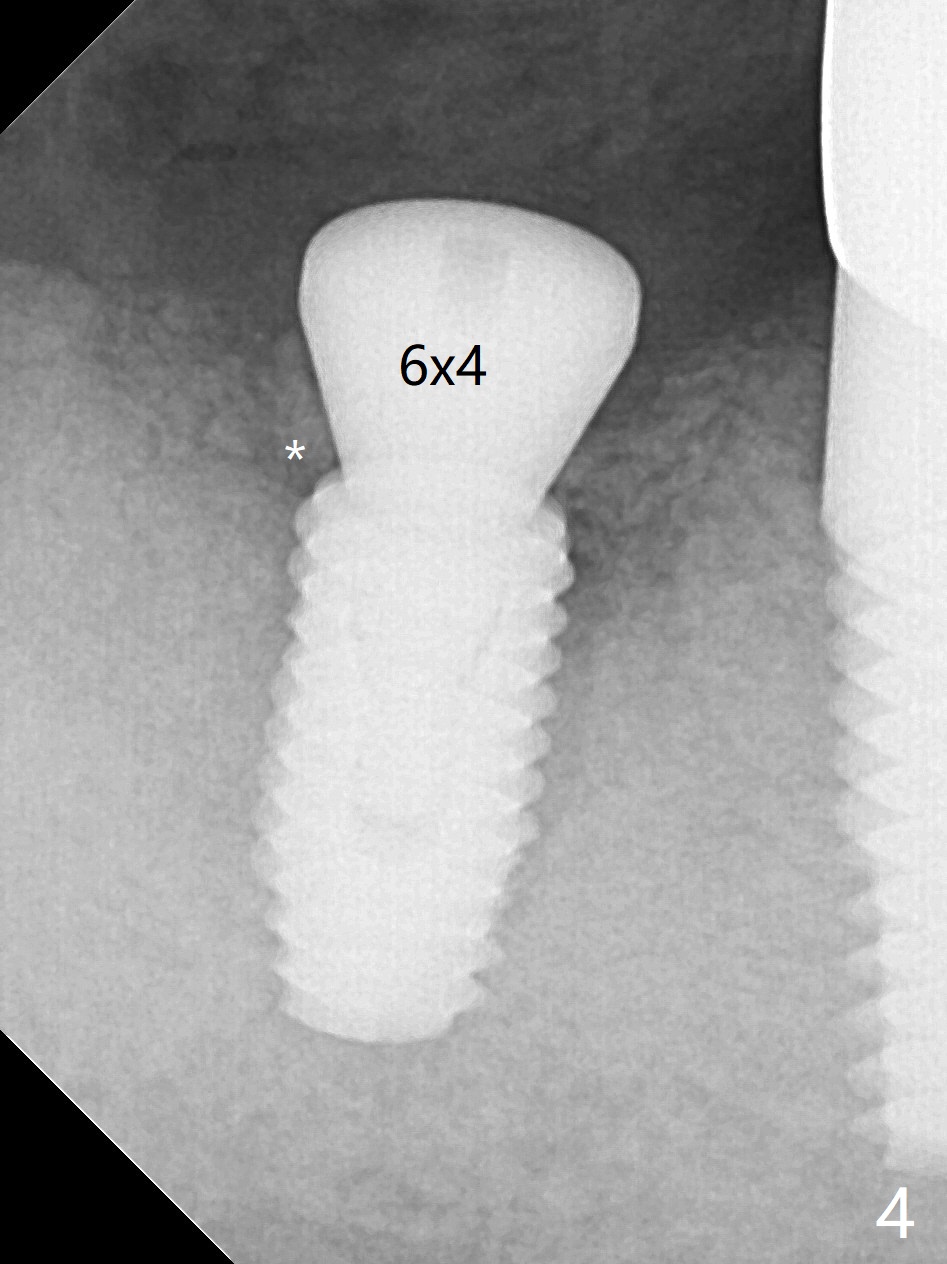

After 2.2x10 mm drill at #31 (Fig.1), bone expansion is conducted with 1.7/3.1 mm and 2.4/3.7 mm Expanders with guide (Fig.2) and 3.0/4.4 mm one without guide. Guided surgery resumes as planned to remove the lingual and apical bone. The buccal bone looks porous from the osteotomy opening. Mixture of autogenous and allograft is packed against the bone plate from the osteotomy before implant placement, but the 5x10 mm implant is unable to be seated completely. After removal of the bone graft from the osteotomy site and use of 4x11.5 mm drill for ~ 1 mm, the implant is seated with ~ 60 Ncm (Fig.3). With buccal incision, bone graft is placed over the distobuccal exposed implant thread (Fig.4 *) following placement of a 6x4 mm healing abutment. Oozing from the wound (thrombocytopenia) is controlled by Polysyn suture and perio glue (Fig.5). The mesial wound dehiscences 7 days postop when DO composite is placed at #28 (Fig.6). Two days later the patient returns because of hemorrhage in brushing. After placement of a taller healing abutment (6x7 mm) with triple antibiotic ointment (although the gingiva cuff is healthy), periodontal dressing is applied. Then the wound heals. The longer healing abutment remains seated (Fig.7 <) without interference from the crest (*) 4.5 months postop. A smaller cemented abutment (5.2x4(4) mm) is chosen with the same outcomes (well seated without gap (Fig.8 < between the implant and abutment), clearance from the crest (*)) 5 months postop. The final crown is cemented 6 months postop with distal access hole (Fig.9 black line), which may be related to design using normal 2nd molar tooth. In fact this patient has small teeth.